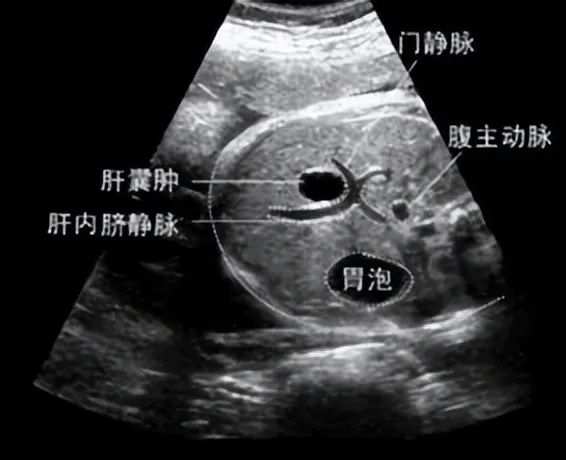

肝囊肿是比较常见的一种肝脏良性病变,小型的肝囊肿发病率是20%,可以说是肝脏里的一个水泡泡,而这个“水泡泡”可以是先天性的(泡泡里面是水)、炎症性的、创伤性的(泡泡里面是血)、寄生虫性的或是肿瘤性的等等。肝囊肿小的又没有症状的,就不需要特殊处理,大部分人是呈现这个情况,基本上不检查不会发现它的存在。而体检查出来的肝囊肿基本上是先天的“水泡”,也不用吃药,吃药一般没用,也不会变小或变没有,所以无需过度担心。

只有肝囊肿过大,如囊肿的直径大于5cm,才值得关注。大到10cm或以上的严重影响到肝脏功能或是对胃、胆、膈肌产生压迫症状,或是不大但能压迫胆管,有感染产生炎症的,表现可能为肚子胀、皮肤黄、肚子疼、发烧、呼吸困难等症状表现,才需要进行治疗。

一般是在B超引导下对囊肿进行穿刺抽液术,或是腹腔镜下囊肿的“开窗术”或叫“去顶术”,或肝叶、肝部分切除术(多发性囊肿),从而减少对肝内管道的压迫。